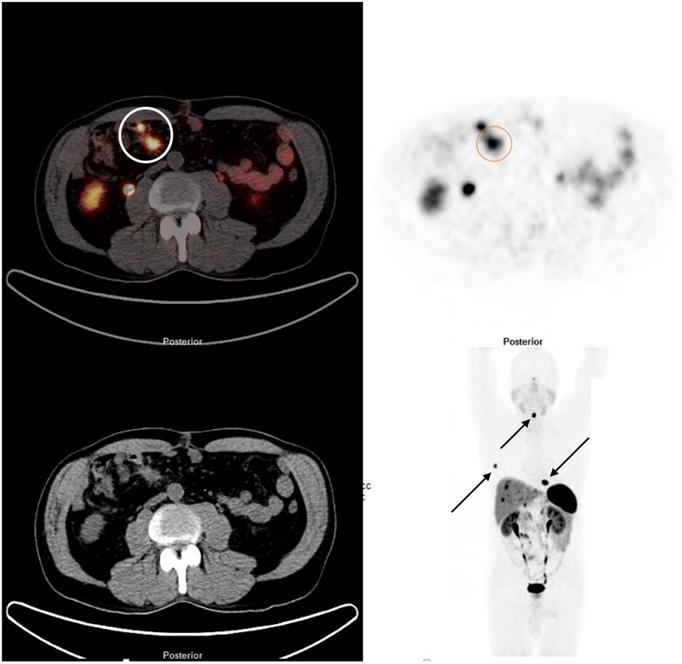

Inclusion criteria were well- or moderately differentiated, grade (G) 1 and G2 NEN originating from small intestine, no previous treatment for NEN apart from injections of high-dose octreotide LAR for amelioration of hormonal symptoms associated with carcinoid syndrome, symptoms caused by loco-regional tumour growth, unresectable stage IV disease, positivity on 68Ga-DOTA-D-Phe1-Tyr3-octreotide (DOTATOC) PET/CT, 68Ga-DOTA-1-Nal3-octreotide (DOTANOC) PET/CT, and 68Ga- DOTA-D-Phe1-Tyr3-Thr8-octreotide (DOTATATE) PET/CT, respectively (Figure 1), absence of severe carcinoid heart disease, eligibility for surgery within four weeks following initial diagnosis, and eligibility for 177Lu PRRT within three months following surgery. Patients who had symptoms of carcinoid syndrome and were referred to us having not yet started treatment for such symptoms were started on octreotide LAR. The treatment was discontinued prior to PRRT with a withdrawal period of 4-6 weeks. Inclusion of patients at ICHCNT was impacted by limited availability of PRRT in UK during the study period. Resectability of liver metastases was assessed with MRI and SSTR-PET/CT. Follow-up encompassed standard biochemistry, morphologic imaging every 3-6 months, SSTR-PET/CT based imaging every 6-12 months, and in a subgroup of patients, blood sampling for NETest prior to surgery and at 6 months after the last PRRT cycle. Overall efficacy of treatment and response to PRRT were assessed with SSTR-PET/CT at 6 months after the last treatment cycle. Outcome measures included 1-, 3-, and 5-year progression-free (PFS) and overall survival (OS) from initial diagnosis. Only patients with a follow-up of at least 6 months were considered.

Figure 1

68Ga DOTATATE PET/CT demonstrating a SBNEN with lymph node metastases and distant metastases. The primary tumour and locoregional lymph node metastases (stage I) are marked with a circle on the fused image (left side) and on the PET component (right side). The patient also had multiple bone metastases (rib, cervical spine and thoracic spine [arrows]) and liver metastases.